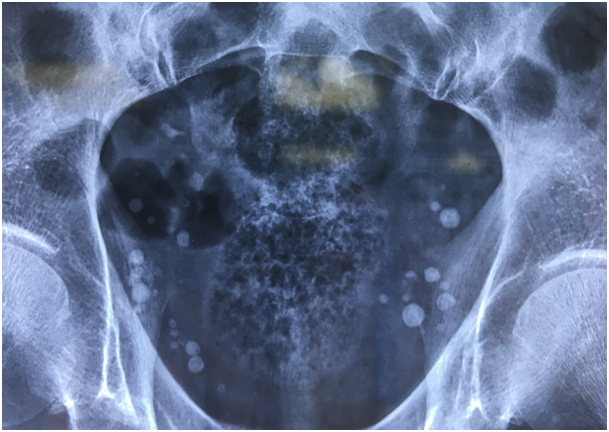

We report the case of Mr. T.O., 56 years old, with no previous medical history, who has been consulting for an abdominal and right low back pain for one week with no digestive sign. A KUB (kidney, ureter and bladder) X-ray showed multiples round calcic images (more than 30) on the pelvic area (Figure 1). An abdomino-pelvic CT-scan showed a 9 mm and 1000 HU pelvic ureteral stone with ipsilateral uretero-hydronephrosis. Extracorporeal shock wave lithotripsy (ESWL), which is indicated, could not be done because of the presence of multiples calcic images, which make the fluoroscopic identification difficult. We put the patient under medical expulsive therapy. The patient expulsed the stone after 22 days.

Figure 1 KUB x-ray showing multiples pelvic phleboliths.

On KUB x-ray, differentiate between phleboliths and ureteral stone is tricky. However, cockade-like with central lucency perfectly round calcic images are more likely to be phleboliths. Enhanced CT scan is the gold standard to differentiate between stone or phleboliths. It can show direct signs of ureteral obstruction. To avoid the contrast agent injection, an unenhanced CT scan can be performed. Three parameters can help in diagnosis: the rim sign if there is a ureteral obstruction (peri-ureteral oedema), the comet sign (the non-calcified vein portion in continuity with the calcification) and the density of the calcification (if inferior to 300 UH, it is more likely to be a phlebolith).